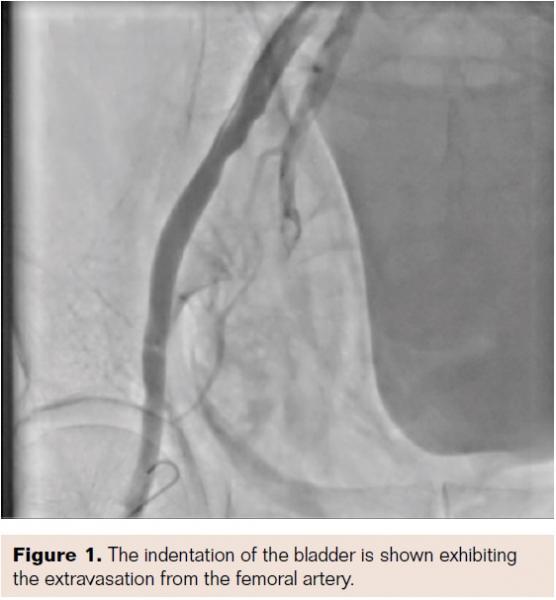

It was noted that the femoral sheath was inadvertently almost out of the body, so it was pushed back into the vessel. However, the patient had severe pain at the puncture site, and a check shot showed that there was extravasation of blood from the femoral artery, out of the sheath into the subcutaneous plane (Figures 1 and 2). The patient had severe hypotension, so although we called the vascular surgeon, we thought we should tackle this by endovascular means.

In our case, the patient developed the complication before he left the lab. We discovered the “indented bladder sign” early after the PCI, so we did a check injection immediately after the patient complained of pain and distress, when the sheath was reintroduced.

As we have shown, bladder compression is a sign of extravasation of blood, but this occurs relatively late after a large volume of blood is lost. So in our patient, a relatively large volume of blood may have collected rapidly to cause profound hypotension and bladder compression.6 Authors have commented that finding the bladder sign in the cath lab allows early detection of a retroperitoneal hematoma and endovascular treatment of the same.7 They and previous authors have called this the dented bladder sign. Routinely looking at the bladder by fluoroscopy for the dented bladder sign after femoral access and a prolonged procedure may prevent late morbidity and mortality from a retroperitoneal hematoma.